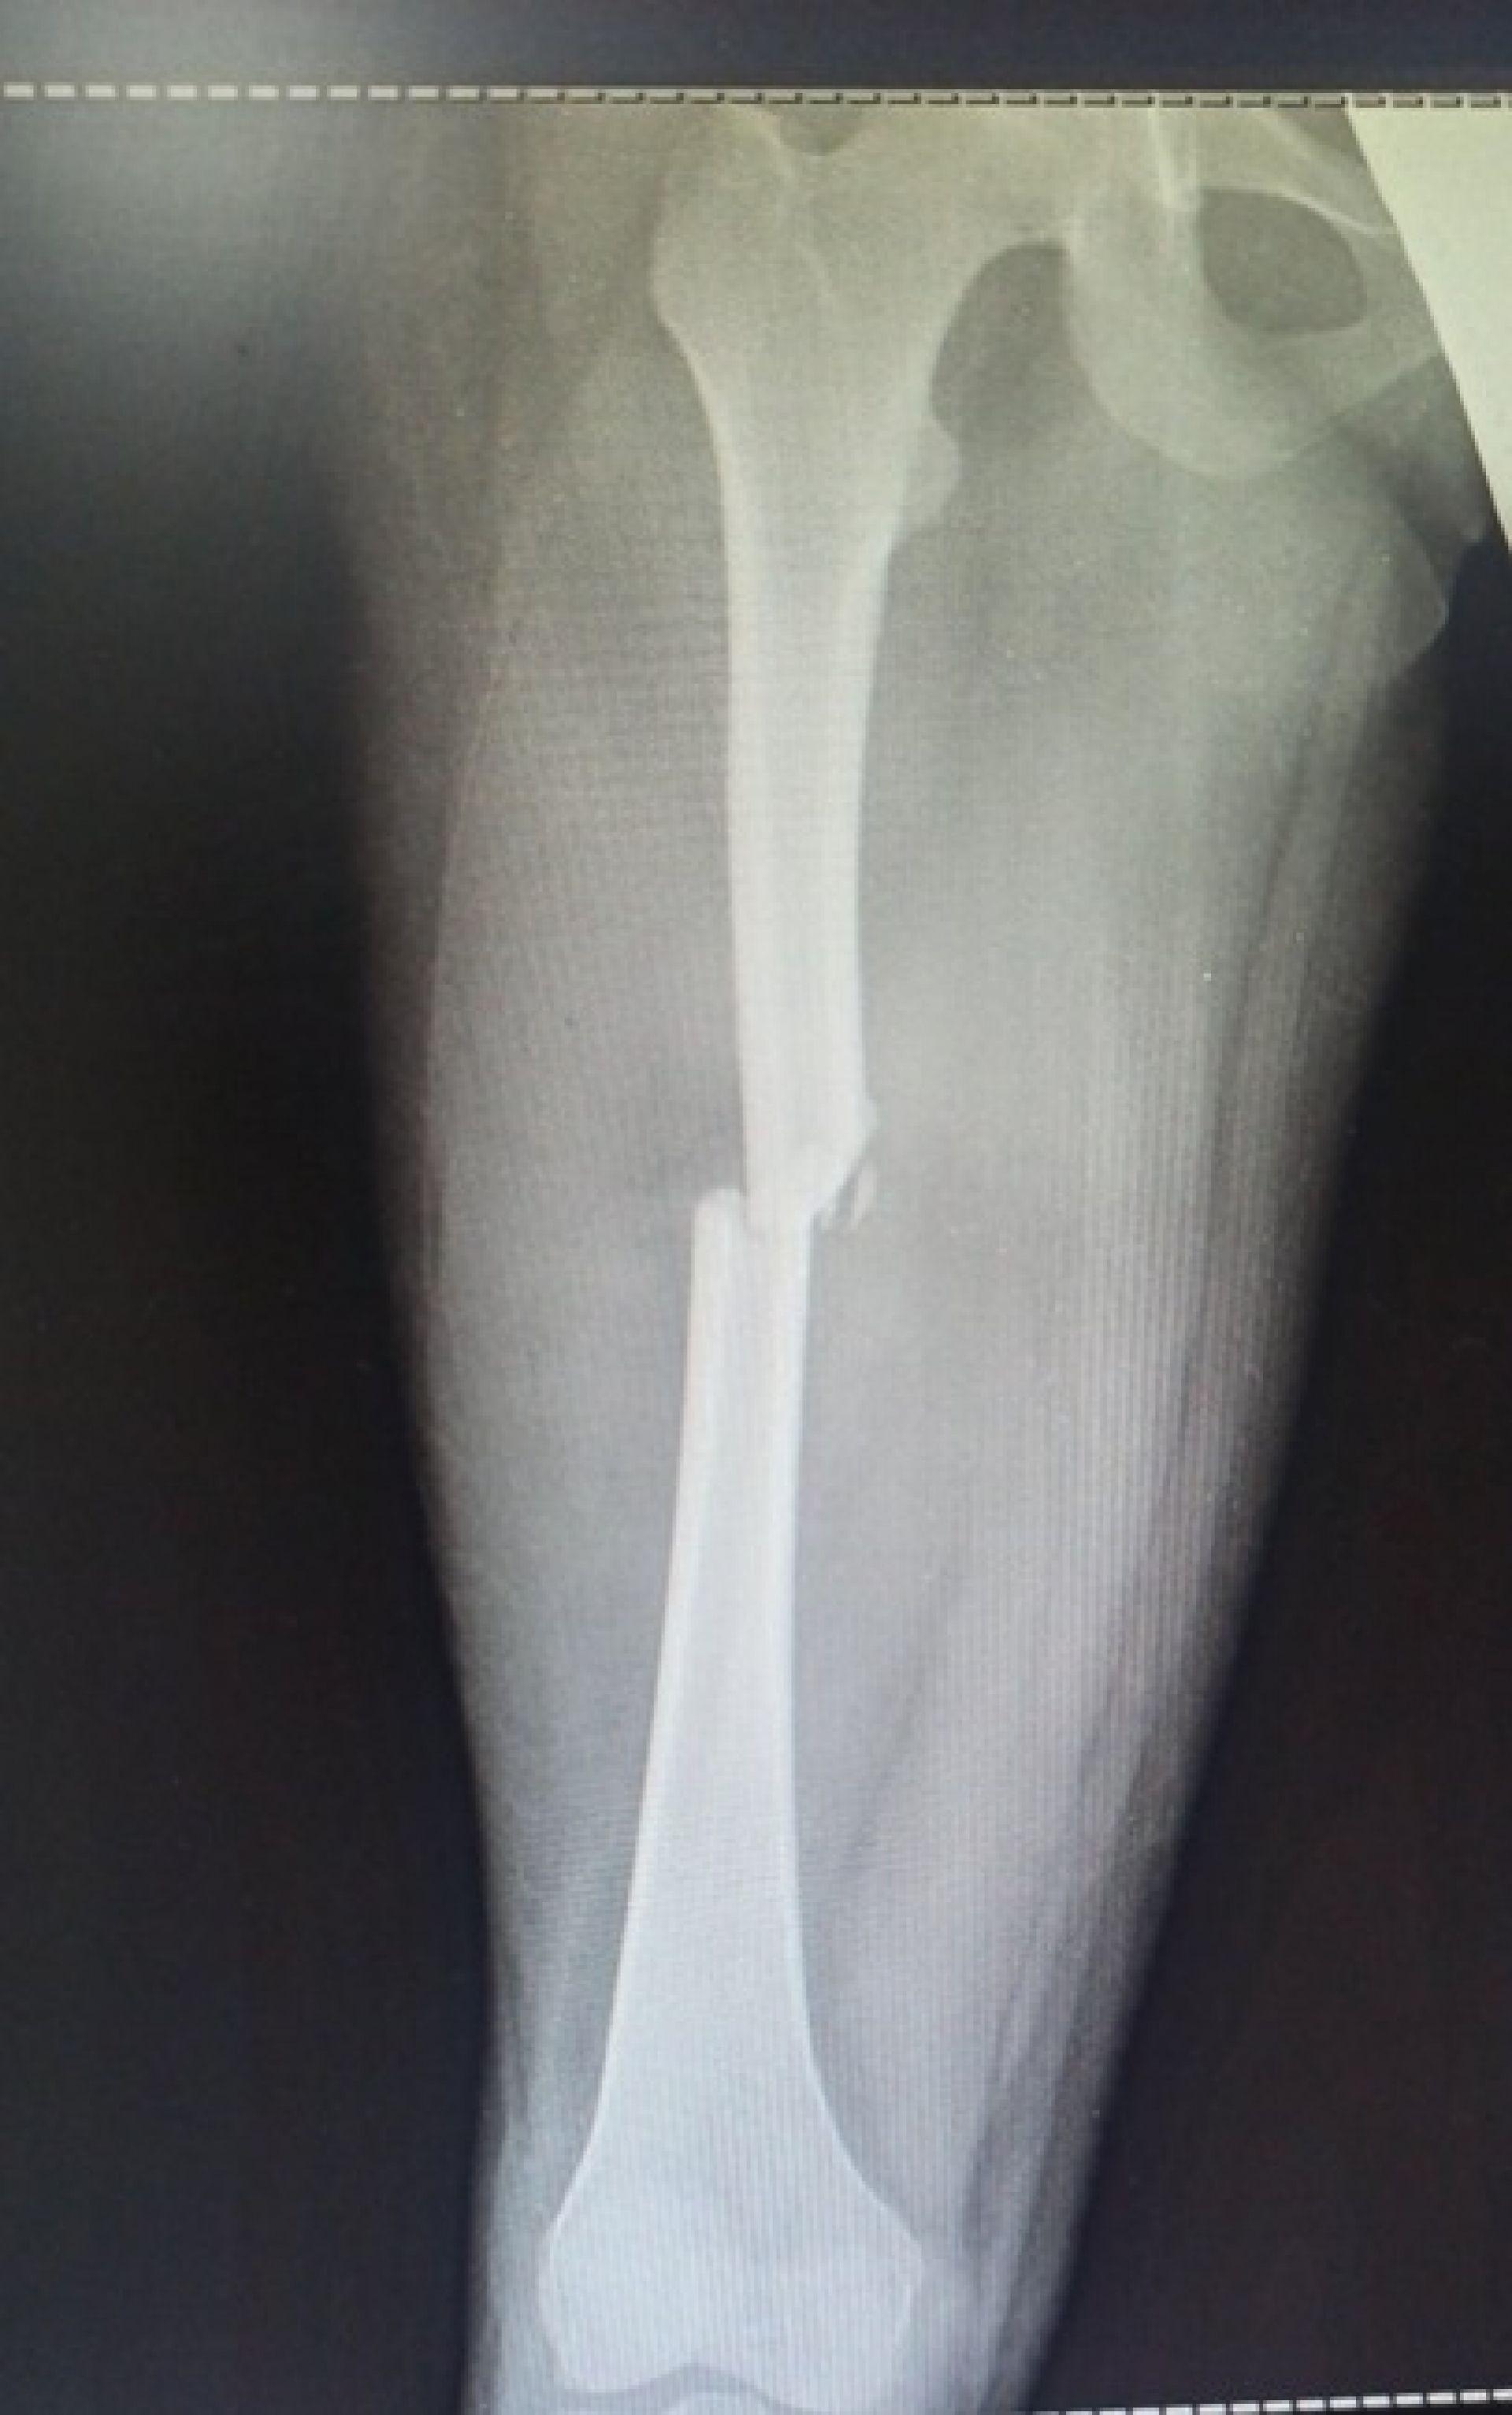

За шість місяців 2025 року до лікарні потрапило 38 дітей, постраждалих у ДТП. Лише за червень таких випадків було 12. Найпоширеніші травми — переломи кінцівок, черепно-мозкові ушкодження, травми хребта та політравми.